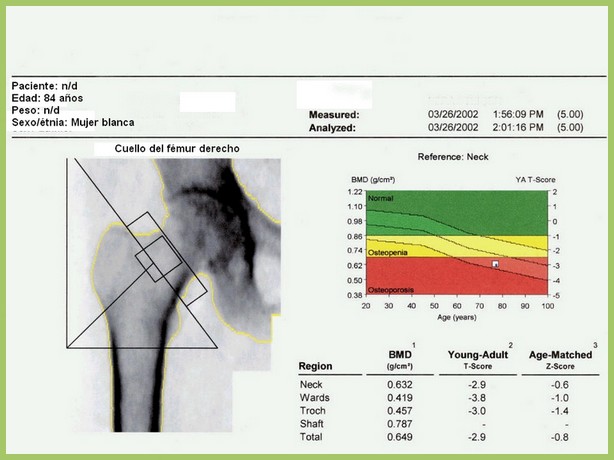

Densitometría ósea: poco cumplimiento de las recomendaciones

En este estudio argentino, la mitad de las densitometrías se pidieron en mujeres que no cumplían los criterios recomendados de edad o de riesgo aumentado para justificar el rastreo de osteoporosis. Salud Colectiva, octubre de 2016